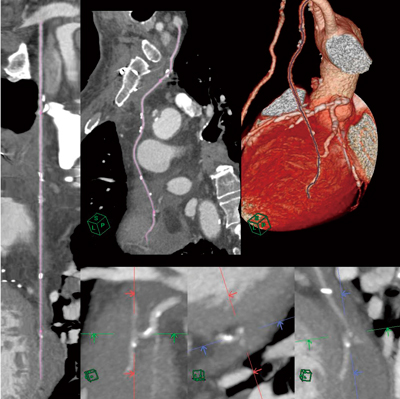

日本循環器学会ガイドライン『冠動脈病変の非侵襲的診断法に関するガイドライン』で,冠動脈CTによる冠動脈バイパス術術後評価に「グラフトの吻合部評価」が挙げられている。今回,AZE社が開発したソフトウェアには,金属製クリップや石灰化病変によるアーチファクトを考慮して血管抽出をするアルゴリズムが搭載されており,in-situグラフト(両側内胸動脈,胃大網動脈)や大動脈‐冠動脈遊離グラフト(橈骨動脈,伏在静脈など)を,1クリックで中枢側起始部から末梢側吻合部まで抽出することが可能となった。また,本来の冠動脈も自動抽出し,その吻合部から末梢の冠動脈の中心線を共有することで,吻合部の確認も容易となる(図2)。そして,吻合部狭窄を確認するために,オブリーク表示では厚みを持たせたslab MIP機能を使用することで,吻合部を明確に表示することができる。さらに,Y-composite型グラフトの遊離動脈を用いたグラフト分枝も認識できる。

図2 冠動脈バイパス吻合部のMIP表示